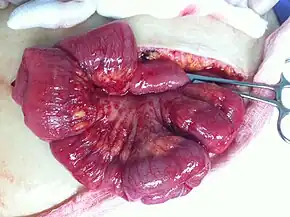

In advanced cancers, where complete removal is not an option, as much tumor as possible is removed in a procedure called debulking surgery. This surgery is not always successful, and is less likely to be successful in women with extensive metastases in the peritoneum, stage- IV disease, cancer in the transverse fissure of the liver, mesentery, or diaphragm, and large areas of ascites. Debulking surgery has usually only been done once[28] but a recent study has shown a longer overall survival in recurrent ovarian cancer when surgery combined with chemotherapy was performed compared to treatment with chemotherapy alone.[95] Computed tomography (abdominal CT) is often used to assess if primary debulking surgery is possible, but low certainty evidence also suggests fluorodeoxyglucose‐18 (FDG) PET/CT and MRI may be useful as an addition for assessing macroscopic incomplete debulking.[96] More complete debulking is associated with better outcomes: women with no macroscopic evidence of disease after debulking have a median survival of 39 months, as opposed to 17 months with less complete surgery.[26] By removing metastases, many cells that are resistant to chemotherapy are removed, and any clumps of cells that have died are also removed. This allows chemotherapy to better reach the remaining cancer cells, which are more likely to be fast-growing and therefore chemosensitive.[29]

There are several different surgical procedures that can be employed to treat ovarian cancer. For stage I and II cancer, laparoscopic (keyhole) surgery can be used, but metastases may not be found. For advanced cancer, laparoscopy is not used, since debulking metastases requires access to the entire peritoneal cavity. Depending on the extent of the cancer, procedures may include a bilateral salpingo-oophorectomy, biopsies throughout the peritoneum and abdominal lymphatic system, omentectomy, splenectomy, bowel resection, diaphragm stripping or resection, appendectomy, or even a posterior pelvic exenteration.[29]